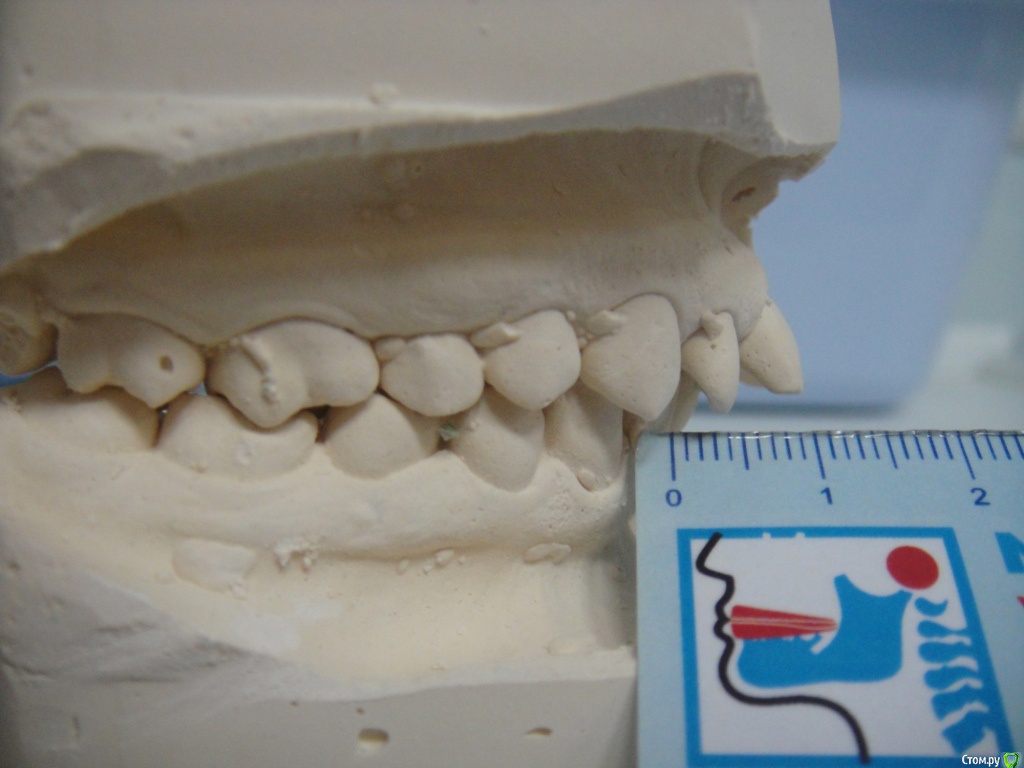

Брекеты ношу 2 месяца, мне 26 лет. Прикрепила фото открытой улыбки уже в брекетах, но так практический никогда не улыбаюсь, неудобно, (торчат два передних зуба) - "рот не открывается"  :D. Еще есть фото зубов с разных сторон, если слепков не хватит, могу добавить.

По Трг Вам однозначно необходимо удаление зубов на в.ч, а возможно и на н.ч т.к очень сильный наклон передних зубов.